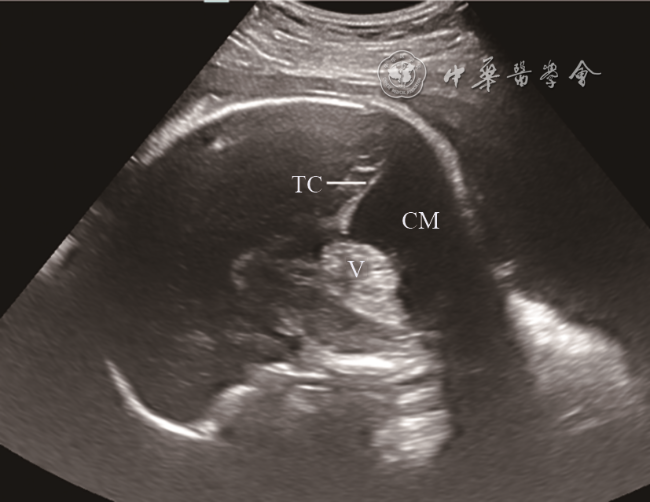

图4 胎儿小脑蚓部发育不良超声声像图(孕34周)。颅脑正中矢状面:小脑蚓部上旋,下蚓部部分缺失,小脑幕位置正常,小脑延髓池增大

注:V为小脑蚓部,TC为小脑幕,CM为小脑延髓池